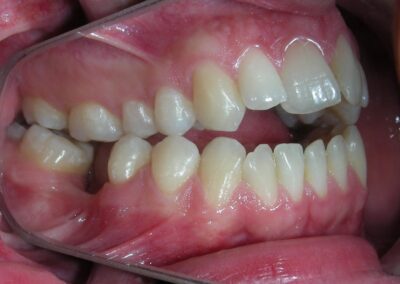

After two years of treatment using appropriate biomechanics, the overbite was successfully corrected from -8 mm to +1 mm, achieving complete closure of the anterior open bite without exacerbating the patient’s lower facial third vertical proportions. At this stage, occlusal contacts were verified using articulating paper, and functional movements of the canines and incisors were evaluated to ensure proper anterior guidance and disclusion patterns. The patient was then referred to speech therapy (myofunctional evaluation) as part of the pre-debond assessment protocol.

Finishing and Retention

At the completion of treatment (28 months) , the patient exhibited significant skeletal and dental improvements consistent with the initial treatment objectives. A reduction of 3 degrees in lower anterior facial height and a 4-degree increase in the facial axis angle were observed on post-treatment cephalometric analysis, indicating a favorable counterclockwise, anterior mandibular rotation. This skeletal change, in conjunction with the mesialization of posterior segments and space closure mechanics, led to the successful resolution of the anterior open bite. During the retention phase, a modified Hawley appliance was used in the maxillary arch, while the mandibular arch was stabilized with a fixed retainer made of twist-flex (supercable) wire #33 to #43 , which had been heat-treated to eliminate its elasticity. This retention strategy was complemented with myofunctional therapy, aimed at ensuring long-term neuromuscular stability.